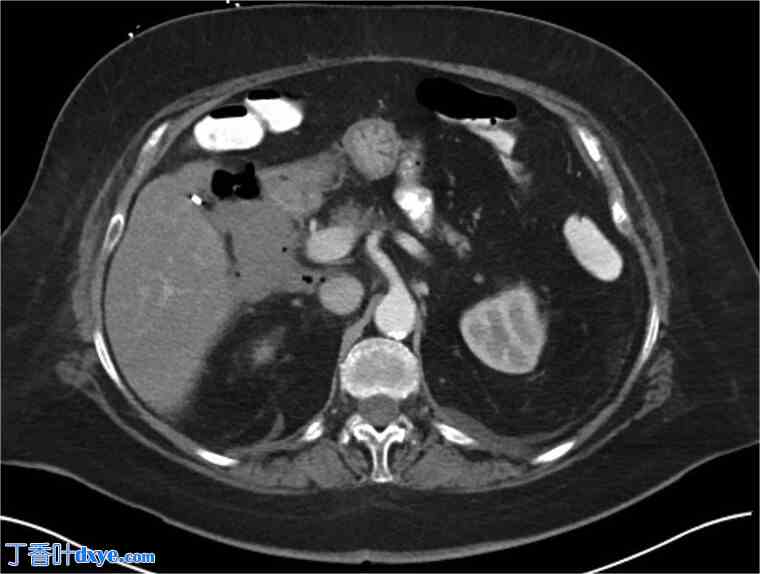

图2.

2.jpg

入院第4天行腹部及盆腔正位CT扫描(口服及静脉注射造影剂),显示散在性气腹及十二指肠侧壁游离液体。